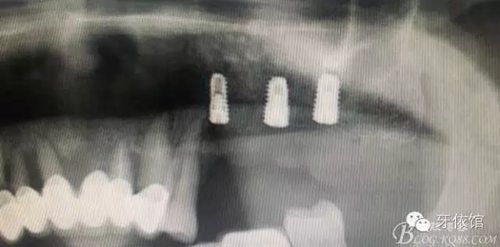

患者男性,62歲,X光片顯示竇底有二維20x15mm囊腫,竇膜內(nèi)無內(nèi)容物

計劃:1.外開窗2.摘除囊腫3.植骨期植入植體

17.webp.jpg

北京種植牙醫(yī)聯(lián)盟特聘講師原解放軍272醫(yī)院口腔科主任2000年開展種植牙專業(yè),年種植量1000顆以上;韓國DIO種植系統(tǒng)外科培訓講師;韓國DENTIS種植系統(tǒng)外科培訓講師;韓國DIO系統(tǒng)、DENTIS系統(tǒng);種植后上部結(jié)構(gòu)修復指導老師;北京種植牙醫(yī)聯(lián)盟理事長;國際種植牙醫(yī)協(xié)會(ICOI)會員。